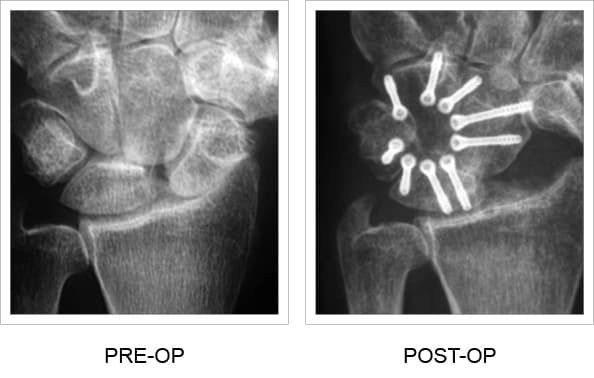

La PEEK Fusion Cup de TriMed se puede utilizar en procedimientos de fusión del metacarpiano y los metatarsianos.

- Fusione varios huesos del carpo o del tarso con una placa de puente de bloqueo de 360 grados avellanada

- La radiotransparencia asegura una colocación óptima del tornillo